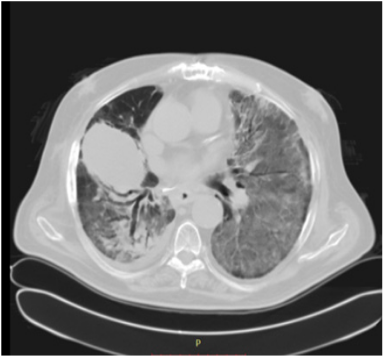

This patient was a 65-year-old man who was admitted to emergency unit in our hospital because he complained of fever refractory to antibiotics, acute severe dyspnea and cough. Saturation O2 was 60%, ERS and D-Dimer title and IL-6 were over the normal range. Swab was positive for SARS-CoV-2. The patient underwent C-pap and intensive ventilation protocol in intensive care unit. The CT images of the chest recorded many diffuse bilateral ground-glass opacities, air bronchogram and interstitial thickening involvement evolving into a whited out lung (Figure 2).

Figure 2 Chest CT scan of Co-19 pneumonia case showing the initial evolution into a bilateral whited out lung.